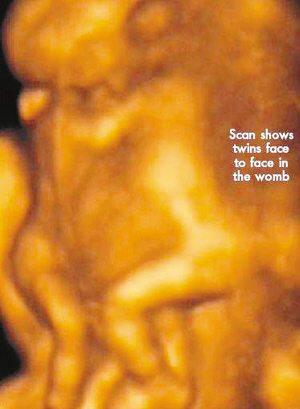

今年初,懷孕7周多的麗莎檢查發(fā)現(xiàn),懷上的竟是一對腹部緊緊相連的連體男嬰。這對連體嬰共享一只肝臟,雖然他們擁有各自的心臟,但兩顆心臟卻粘連在了一起。醫(yī)生建議麗莎立即接受流產手術,他認為麗莎腹中的連體嬰甚至無法活到她懷孕10周的時候。

麗莎每周都要到醫(yī)院接受醫(yī)學掃描,而她腹中的連體嬰也讓醫(yī)生感到驚訝不已,因為他們已經打破了醫(yī)生的死亡預言,一直在母親子宮中堅強活到了現(xiàn)在。麗莎將于兩周內接受剖腹產手術。